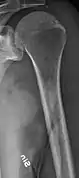

Medical imaging

The diagnostic examination of a person with suspected multiple myeloma typically includes a skeletal survey. This is a series of X-rays of the skull, axial skeleton, and proximal long bones. Myeloma activity sometimes appears as "lytic lesions" (with local disappearance of normal bone due to resorption) or as "punched-out lesions" on the skull X-ray ("raindrop skull"). Lesions may also be sclerotic, which is seen as radiodense.[70] Overall, the radiodensity of myeloma is between −30 and 120 Hounsfield units (HU).[71] Magnetic resonance imaging is more sensitive than simple X-rays in the detection of lytic lesions, and may supersede a skeletal survey, especially when vertebral disease is suspected. Occasionally, a CT scan is performed to measure the size of soft-tissue plasmacytomas. Nuclear Medicine Bone scans are typically not of any additional value in the workup of people with myeloma (no new bone formation; lytic lesions not well visualized on nuclear bone scan).

Bone pain affects almost 70% of people with multiple myeloma and is one of the most common symptoms.[2]:653[22] Myeloma bone pain usually involves the spine and ribs, and worsens with activity. Persistent, localized pain may indicate a pathological bone fracture. Involvement of the vertebrae may lead to spinal cord compression or kyphosis. Myeloma bone disease is due to the overexpression of receptor activator for nuclear factor κ B ligand (RANKL) by bone marrow stroma. RANKL activates osteoclasts, which resorb bone. The resultant bone lesions are lytic (cause breakdown) in nature, and are best seen in plain radiographs, which may show "punched-out" resorptive lesions (including the "raindrop" appearance of the skull on radiography). The breakdown of bone also leads to the release of calcium ions into the blood, leading to hypercalcemia and its associated symptoms.[23]